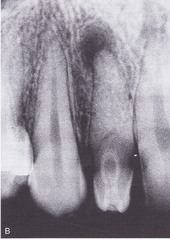

internal resorption

-round to ovoid radiolucency in the central part of the tooth -chronic inflammation -may see pinkish hue to crown if it is involved